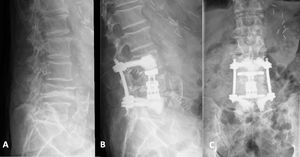

A modo de ejemplo, elegimos la técnica descrita para un paciente de 81 años que acudió a nuestra clínica con fractura patológica en L4 debido a carcinoma bronquial metastásico (fig. 2). Tras la radioterapia se produjo una compresión e inestabilidad progresivas del cuerpo vertebral como resultado de la necrosis vertebral inducida por la radiación. Debido a la estenosis sintomática del canal espinal concomitante con ciática lumbar derecha a causa de estenosis del receso lateral neuroforaminal y lateral, se realizó espondilodesis percutánea dorsal de L3 a L5 con tornillos pediculares cementados, junto con hemilaminectomía dorsal de la cuarta vértebra lumbar con facetectomía y descompresión de las raíces nerviosas de L4 y L5 derechas. Posteriormente, tras recolocar al paciente, se realizó VBR (Obelisk, Ulrich Medical) con cementación de las placas terminales bajo visión directa, según lo descrito previamente42. Transcurridos diez días postoperatorios, el paciente recibió el alta para tratamiento ambulatorio. Las revisiones de seguimiento reflejaron un resultado satisfactorio.

Otro caso implicó a una paciente de 71 años que acudió tras caerse de un caballo, sosteniendo una fractura traumática de T12 (fig. 3). Las radiografías revelaron escoliosis lumbar degenerativa (ángulo de Cobb de 19°). A pesar de tener una puntuación T de -1,9, optamos por fijar el segmento corto con cemento para esta paciente móvil y activa, y debido a los traumatismos axiales recurrentes a causa de la equitación, decidimos realizar la cementación adicional de las placas terminales. El procedimiento se realizó en dos etapas, sin complicaciones. Transcurrido un año postoperatorio, la paciente reportó ser capaz de montar a caballo sin restricciones y, a pesar de la fusión del segmento corto en la unión toracolumbar, el seguimiento más reciente transcurridos cinco años reflejó un resultado clínico y radiológico satisfactorio, sin problema alguno.

Fractura traumática en T12. A/B) TC preoperatoria. C/D) TC postoperatoria tras fijación del segmento corto con tornillos pediculares cementados y VBR con cementación de la placa terminal. E) Rayos X en bipedestación (plano coronal) durante el último seguimiento. La escoliosis lumbar permaneció constante. La paciente fue plenamente funcional, sin limitaciones de la vida diaria transcurridos cinco años postoperatorios.